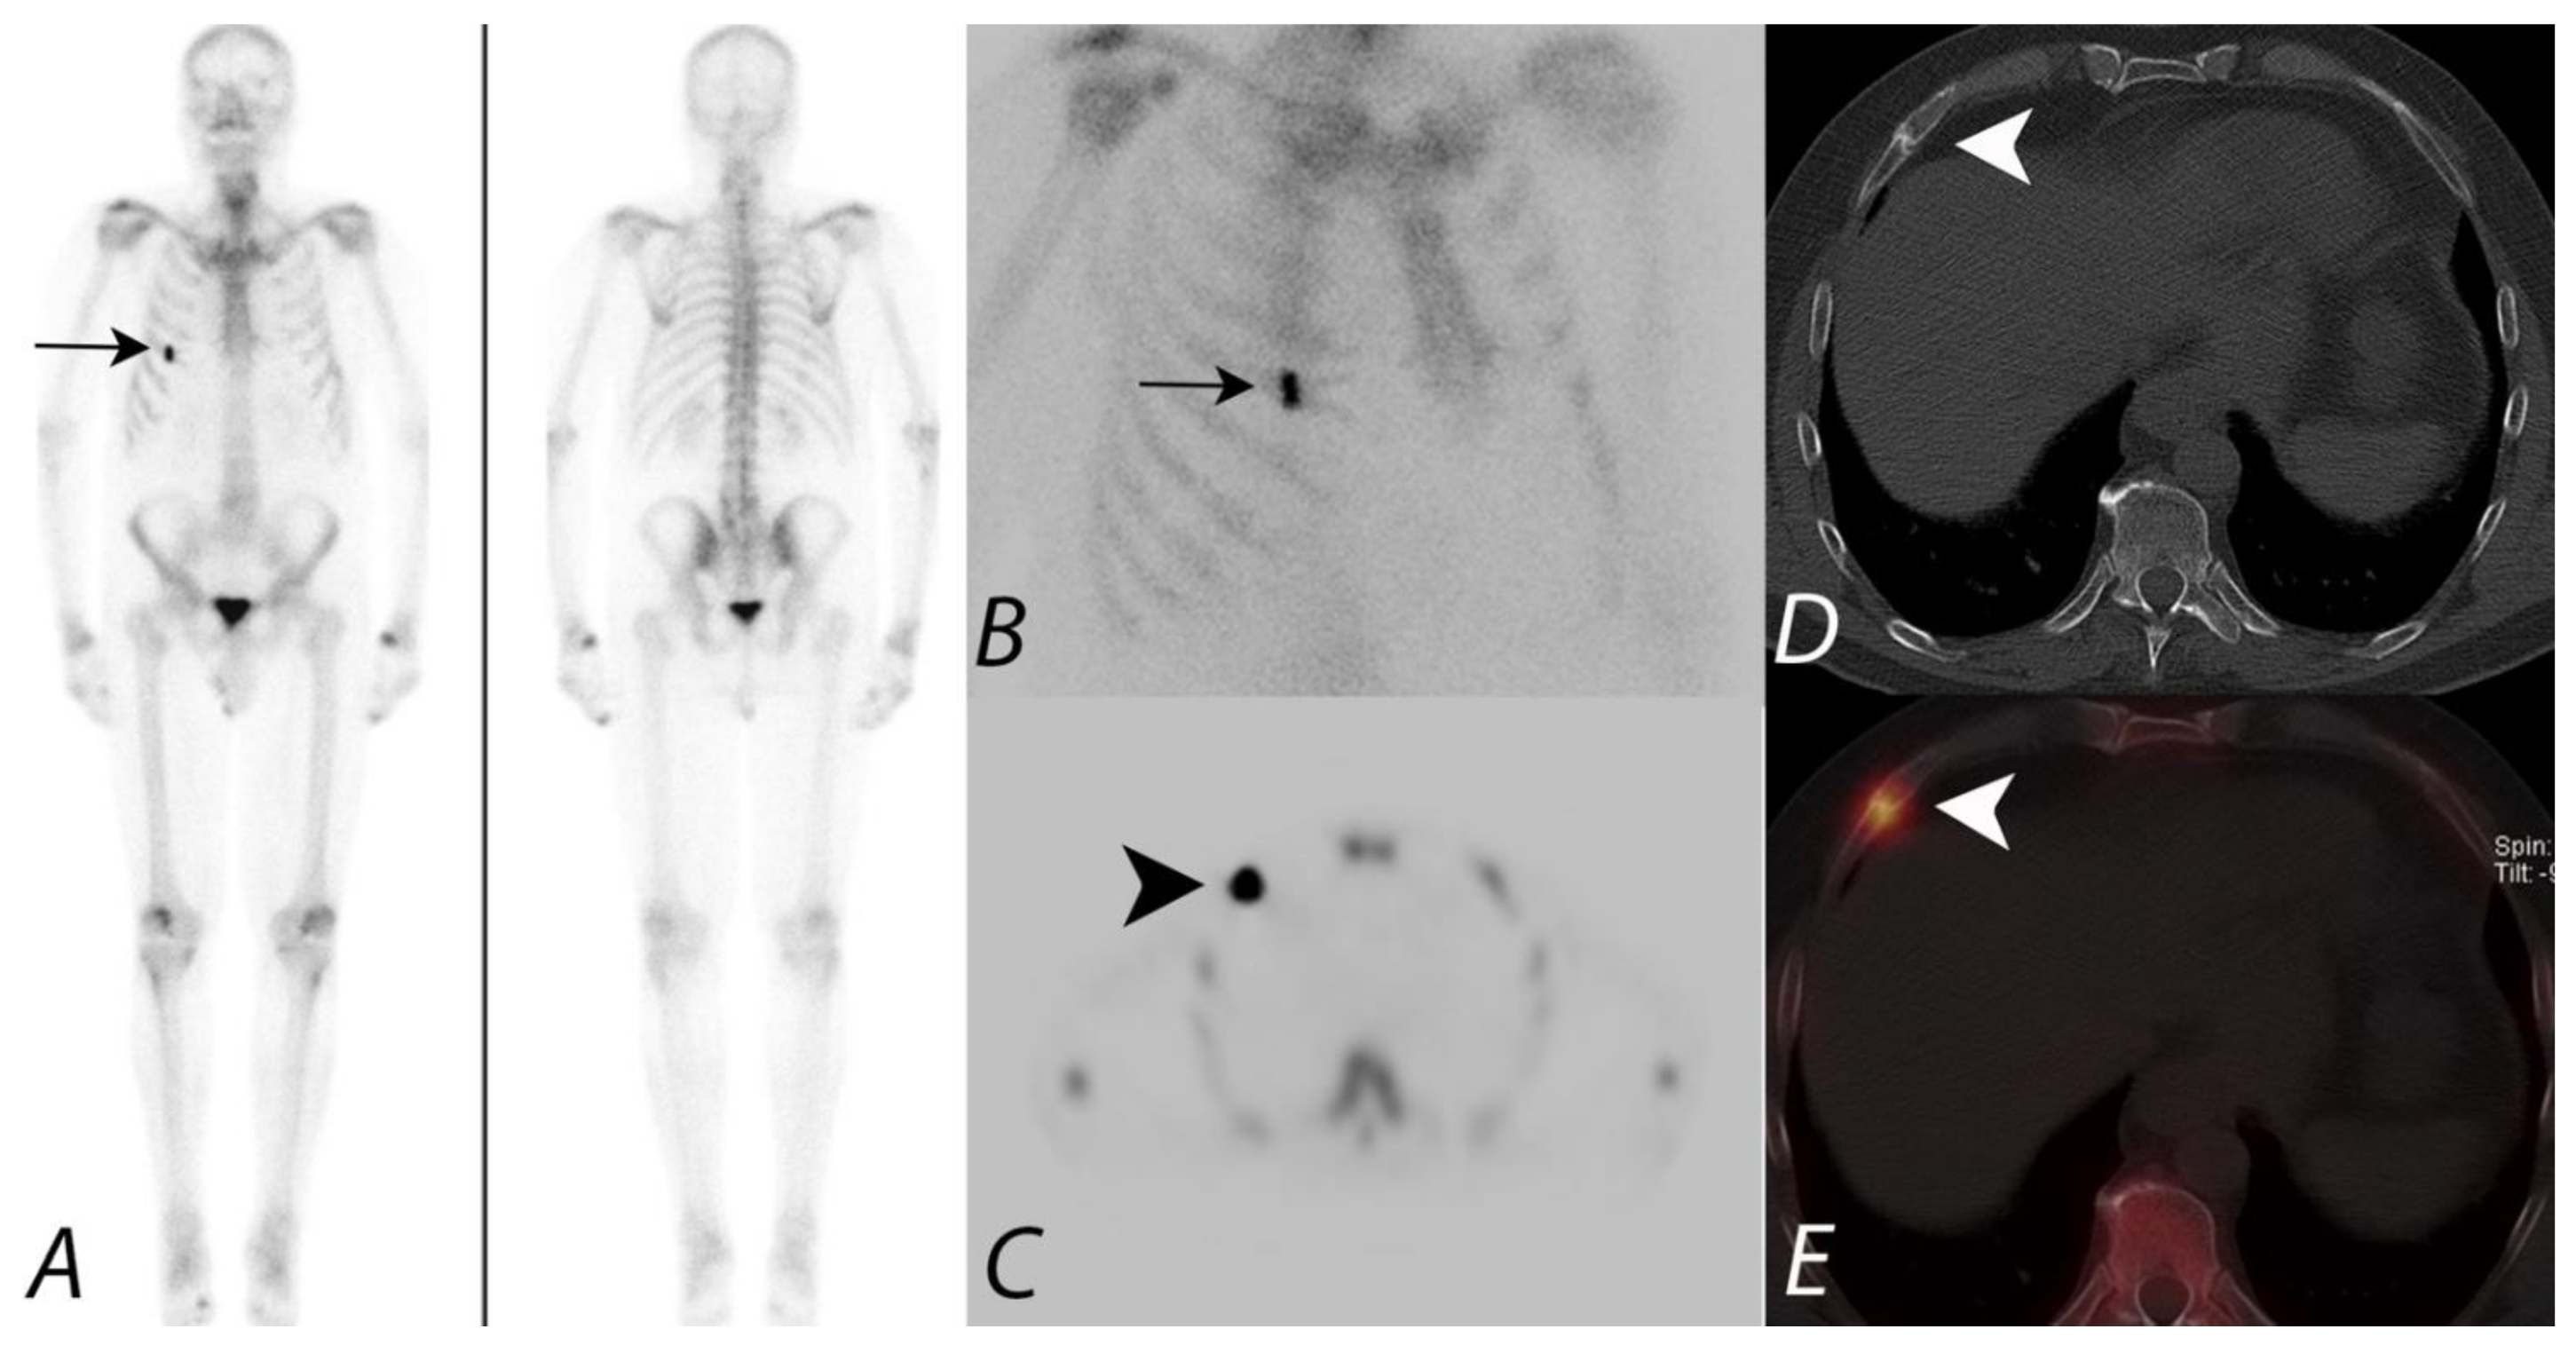

Figure 3.

Anterior and posterior whole body 99mTc MDP bone scan planar images (A) from a Tc-99m MDP bone scan in a 68-year-old male with prostate cancer and new pelvic pain demonstrate focal uptake (black arrows) localizing to the left sacral region. Coronal CT and fused SPECT/CT images (B,C) demonstrate the uptake localizing to a vertical insufficiency fracture of the left sacral ala, which demonstrates osteoblastic activity, confirming a healing insufficiency fracture and not metastatic disease.

Multiple studies have reported increased viewer confidence in interpretation by using the fusion of SPECT data with CT data when compared to SPECT alone or by side-by-side interpretation of anatomic imaging information from CT and scintigraphic data [32,33]. A comparative study of planar scintigraphy, SPECT, and SPECT-guided CT, digitally fused with 64-slice MSCT images in 37 patients with 42 focal bone lesions of the axial skeleton, reported the fused images to significantly increase diagnostic specificity [34] A specific diagnosis was made with planar scintigraphy in 64% of cases, SPECT in 86%, and SPECT fused with CT in all cases. The addition of SPECT/CT greatly improves the diagnostic value of Tc-99m bisphosphonate bone scans over that of planar imaging only (Figure 4).

Figure 4.

Anterior and posterior planar images (A) from a 99mTc MDP bone scan on a patient with prostate cancer being evaluated for metastatic disease, with focal uptake along the right aspect of lumbar spine (black arrows). Additional focus of uptake involving the distal right tibia is related to a known fracture involving this region. No additional foci of uptake concerning metastatic disease were identified. Sagittal CT image and fused SPECT/CT images in sagittal and coronal projections (B–D) localize the activity to the right aspect of the disc space between L2 and L3, correlating with disc space narrowing and osteophytosis (white arrowhead). Findings are consistent with uptake related to degenerative disc disease and not related to metastatic disease.